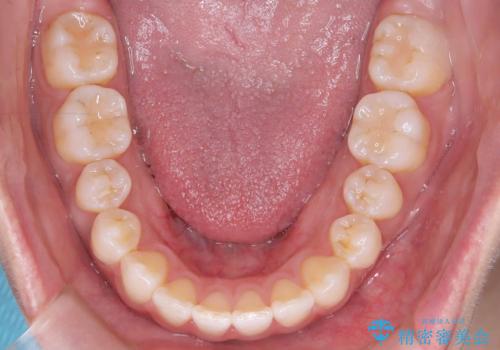

その結果、約10ヵ月という比較的短期間で歯列と咬み合わせが整い、機能面・審美面ともに良好な結果を得ることができました。